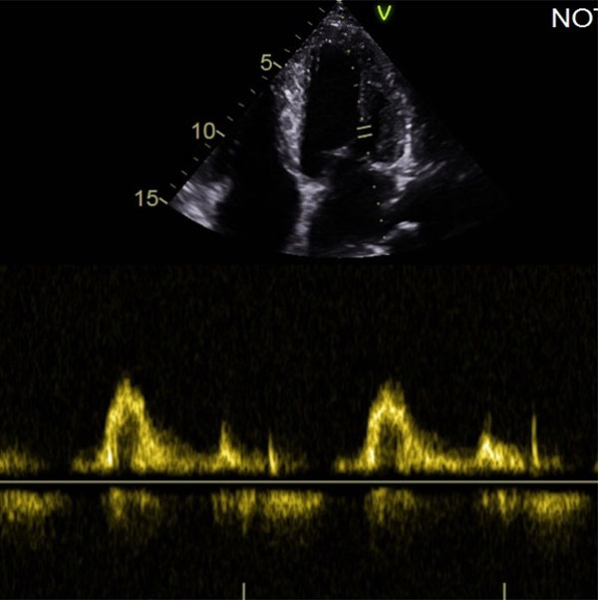

ETT :

- Hypertrophie ventriculaire gauche à prédominance septale (SIVd 12 mm, PPVG 12 mm) sans obstruction de repos, de fonction systolique conservée à 60 % en Simpson biplan. Cinétique homogène, SLG altéré à - 16 % en cocarde

- VD fin de bonne fonction longitudinale

Vidéo 4 : Sous costale

Figure 7 : E' latéral 7,8